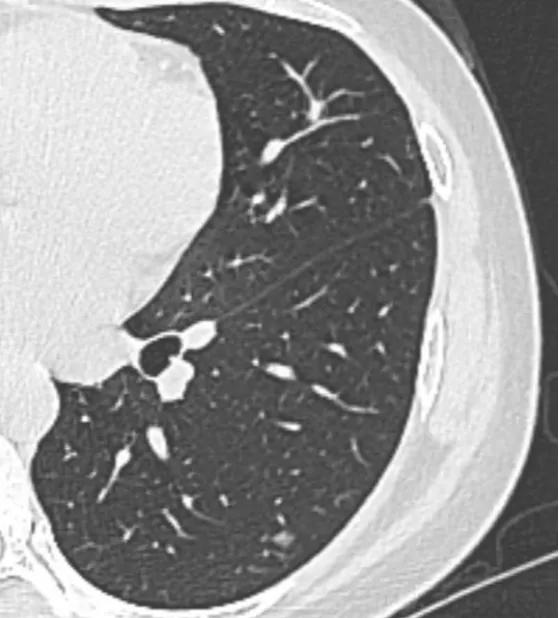

就像今天这位来自南昌的妹子,查出磨玻璃结节后焦虑不已,虽然在贴吧问诊的时候我已经详细地回复过,表示没事,可控可根治,但这没能让她安心,还是认为只有亲耳听到确切的诊断后才能放心,所以毅然加号来重庆面诊。根据她的报告和各种检查结果来看,我还是断定所有结节暂时都还是安全的,我表示还可以继续随访,半年到一年复查一次,说不定三五年都不会有事。

既然这次已经当面听过诊断了,下一次可以不用跑这么远过来了,太辛苦了,直接在当地拍片后在贴吧找我看片就可以了,只要盯住左边那个结节,没长大2-3mm就是安全的。谢谢您的信任。

“右边结节看着还好欸,好淡,安全的,介于非典型增生到原位之间,左边这个小的反而要留意下,介于原位到微浸润之间,大概率原位,小概率微浸润。半年到一年复查一次,盯住它就是安全的。心理压力大也可以选择切掉!” “主任那您看呢?现在有必要手术吗?我都听您的。”“要不再纠结纠结?盯住它,先回去吧!说不定三到五年都没事!”

动车已经慢慢驶出重庆了,再次引用17年离渝我朋友圈那段话,人生是不断地相识,离别又重逢,再见了美丽的重庆,伟大的戴主任, 因为有您这样伟大的守护神,重庆,不久又会再见的。主任,保重身体!因为昨天太紧张忘记问您,像右下肺这个8mm左右的结节,是不是可以理解为良性?截图感觉这个结节中间有实性白点有没有关系?再次谢谢您!!